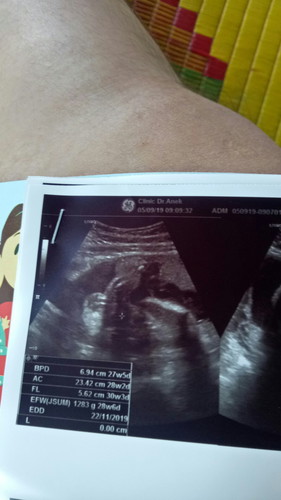

มีสิทธิ์ได้ลูกผู้ชายไหมค่ะหมอบอกเหมือนมีหำ

หมอบอกเหมือนเหนไข่น้องค่ะแต่แม่ไม่แน่ใจ

น่าจะผู้ชายค่ะ